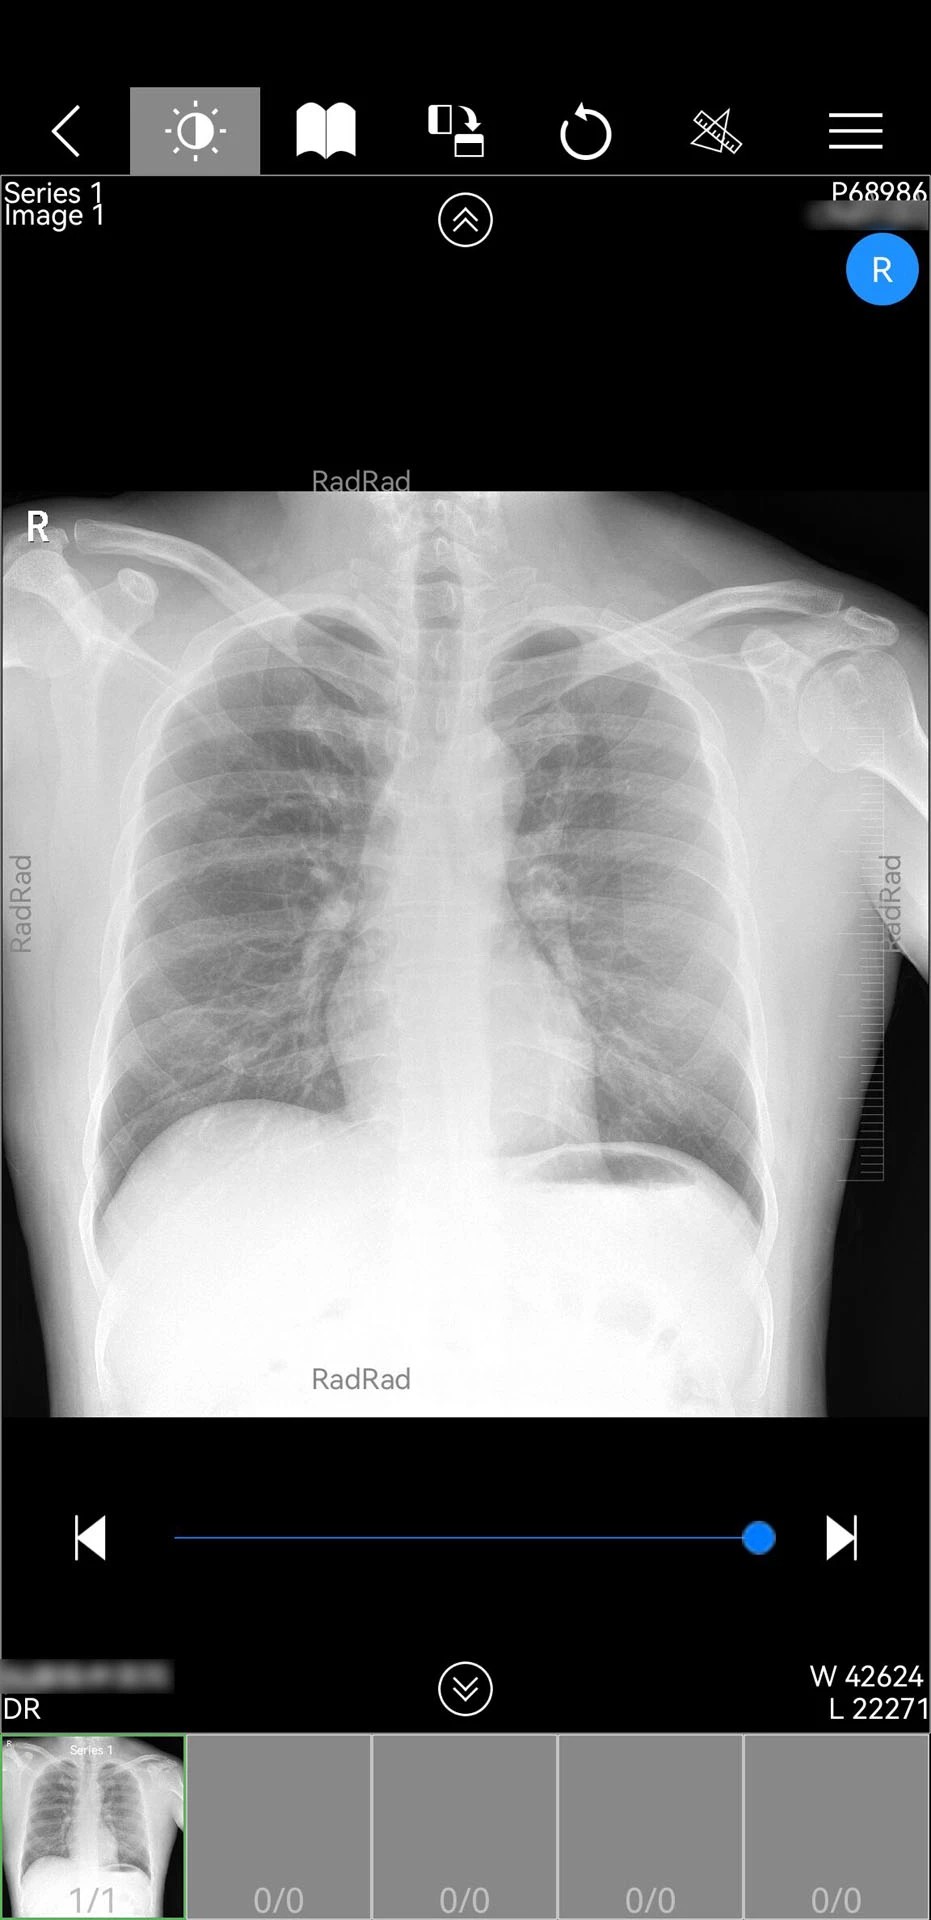

2. AI辅助诊断系统:内置深度学习算法,可自动识别肺结节、骨折等常见病变,标注疑似病灶并生成结构化报告,减少人工阅片时间,提升诊断一致性。

5. 多设备兼容性:适配手机、平板、电脑等多终端,支持DICOM格式原生解析,无需额外插件,确保影像显示精度与操作流畅度。

1. 提升诊断效率:AI辅助阅片将平均诊断时间从15分钟缩短至3分钟,复杂病例会诊响应速度提升50%,显著缓解影像科医生工作压力。

微影医生全新版本在功能完整性、技术先进性与用户体验方面均达到行业领先水平。其AI影像分析准确率经临床验证达92%,三维重建速度较传统软件提升3倍,尤其适合影像科医生日常使用。用户反馈显示,软件操作界面简洁直观,新手医生也能快速上手;跨院协作功能有效打破了地域限制,提升了基层医疗服务能力。然而,部分用户指出,APP在iOS设备上存在验证码显示异常问题,且缺乏历史数据清理功能,可能导致存储空间占用过大。总体而言,微影医生凭借其强大的影像处理能力与协作生态,成为影像科医生不可或缺的数字化工具,未来若能进一步优化跨平台兼容性与数据管理功能,将更具竞争力。